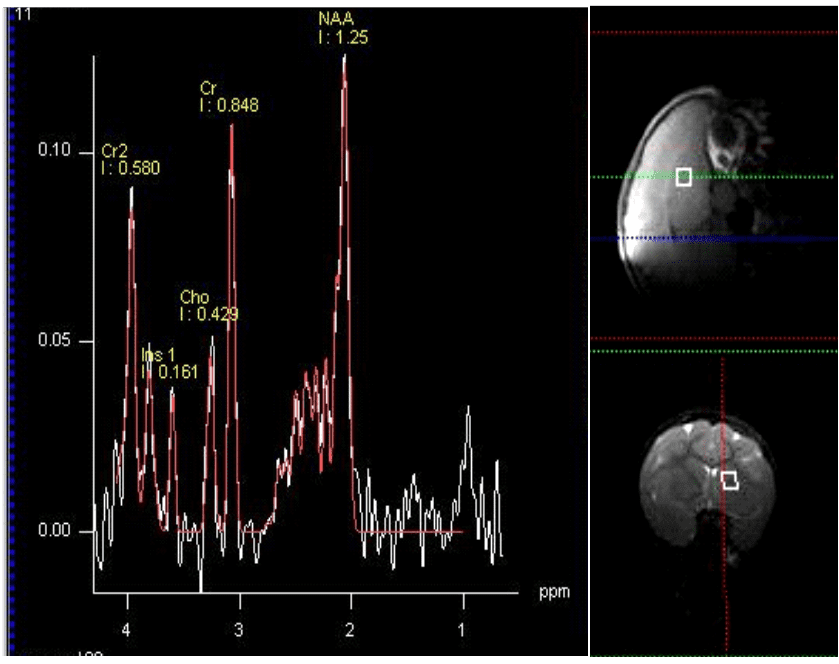

La espectroscopia por MR es ideal para mediciones repetidas y para medir resultados terapéuticos mediante la obtención de señales químicas o metabolitos de una región de interés. Se genera un espectro de picos, por lo que cada pico refleja un producto químico que resuena a una frecuencia específica (descrita en partes por millón o ppm); la altura del pico refleja la concentración de ese químico en el cerebro (descrito como una proporción de creatina, unidades institucionales o concentración milimolar).

Con la espectroscopia MR se pueden detectar diferentes metabolitos y sus funciones biológicas se pueden utilizar para proporcionar una perspectiva fisiopatológica para el diagnóstico y la monitorización del tratamiento.